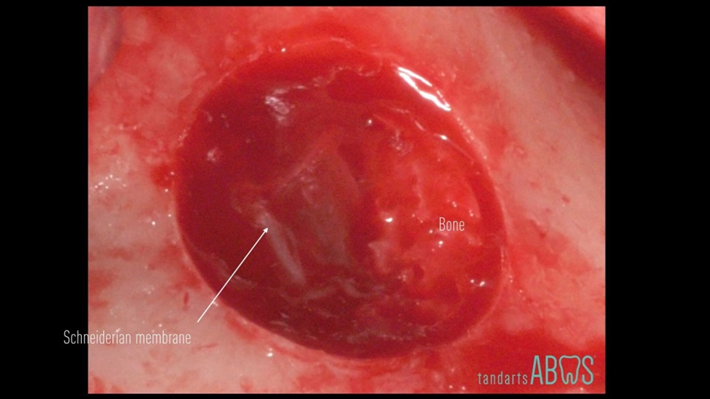

Clinical case: Delayed implant placement: sinus floor elevation by means of lateral

approach & implant placement with GBR

- Courtesy of Dr. Irfan Abas, Netherlands -